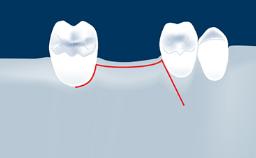

Digitally Guided Sinus Floor Elevation

• describe the indications for digital guides in SFE